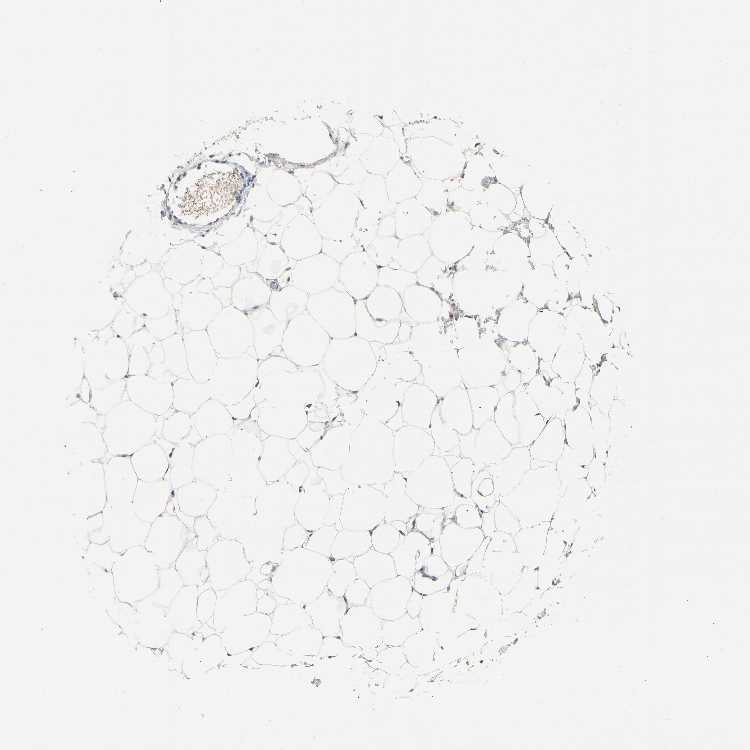

SOFT TISSUE 1 - Antibody stainingi

Antibody staining in the annotated cell types in the current human tissue is reported as not detected, low, medium, or high, based on conventional immunohistochemistry profiling in selected tissues. This score is based on the combination of the staining intensity and fraction of stained cells.

Each image is clickable and will lead to virtual microscopy that enables deeper exploration of all samples and also displays staining intensity scores, fraction scores and subcellular localization as well as patient and tissue information for each sample.

Antibody HPA006735Antibody HPA017142

Chondrocytes Medium-

Fibroblasts LowNot detected

Peripheral nerve -Not detected